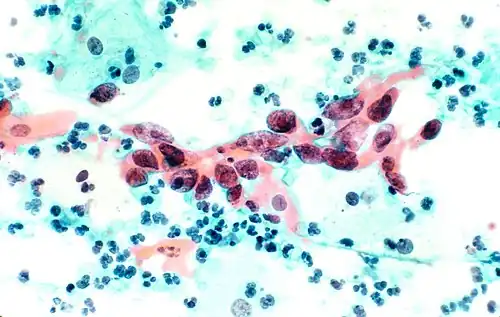

В результате окрашивания по Папаниколау клетки остаются прозрачными. Ядра клеток принимают цвет от синего до чёрного. Цитоплазма окрашивается в сине-зеленый цвет; кератин — в оранжевый.

Эозин Y окрашивает поверхностный плоский эпителий, ядрышки, реснички и эритроциты. Светло-зеленый SF желтоватый придает голубое окрашивание цитоплазме призматических, парабазальных плоских и промежуточных плоских клеток. Поверхностные клетки окрашиваются от оранжевого до розового, а промежуточные и парабазальные клетки становятся бирюзово-зелеными или голубыми[6].

Плоскоклеточная карцинома, бронхоальвеолярный лаваж.

Клетки меланомы, тонкоигольная аспирационная пункционная биопсия печени.

Папиллярный рак щитовидной железы, тонкоигольная аспирационная биопсия.

Плоскоклеточная карцинома шейки матки.